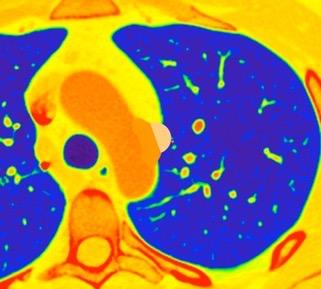

Triada de Garland

Ganglios paratraqueales derechos e hiliares bilaterales

95% de pacientes tienen ganglios hiliares bilaterales aislados o con afectación mediastínica (espec. paratraqueal derecho).

Criado E et al. Pulmonary sarcoidosis: typical and atypical manifestations at high-resolution CT with pathologic correlation. Radiographics. 2010